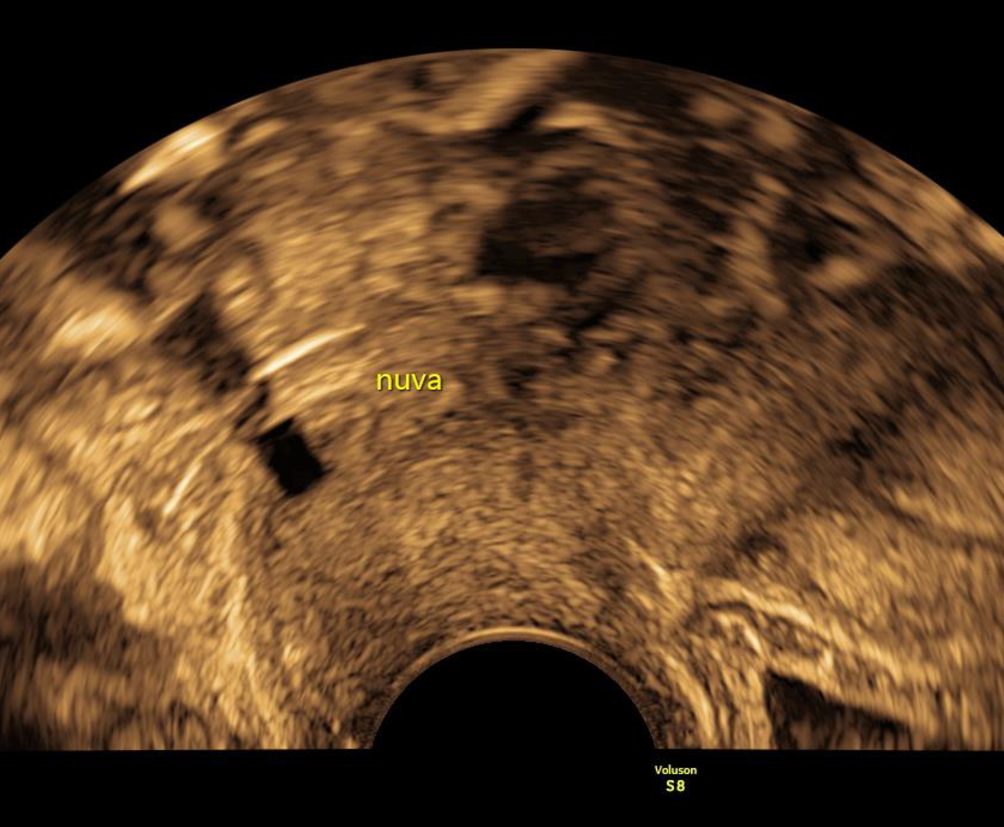

NuvaRing

Zum Abschluss sollte noch der NuvaRing erwähnt werden, der ein charakteristisches sonographisches Erscheinungsbild aufweist – im normalen Schnittbild hat er eine nahezu rechteckige Form, hinter der ein Schatten liegt, wie man ihn von Hormonspiralen kennt (Abb. 7). Es gibt Fallberichte von Anwenderinnen, die den NuvaRing versehentlich in der Harnblase platzierten, dieser kann mit entsprechend gefüllter Blase im Ultraschall gesehen und zystoskopisch entfernt werden [8].

Abb. 7

Ein NuvaRing imponiert als rechteckiger, echoarmer Block unmittelbar hinter der Zervix